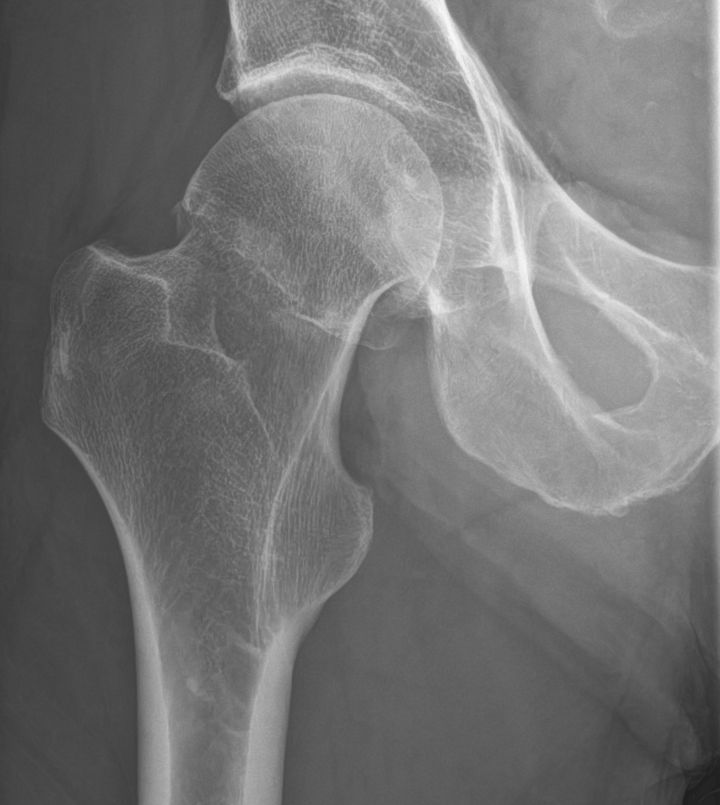

- Cervikal, fraktur av kollum femoris. Klassificeras enligt Garden som bedöms på frontalbild. Det finns något olika tolkningar av denna klassifikation. Ofta används istället "Garden 1-2" för odislocerad eller måttligt dislocerad fraktur och "Garden 3-4" för mer dislocerad.

- Garden 2: genomgående fraktur utan annan felställning än kompression [1]